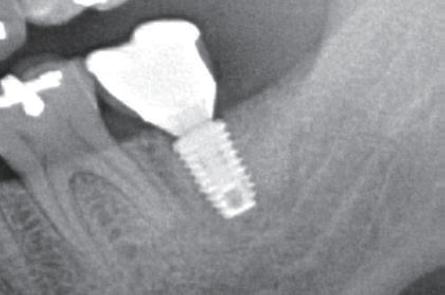

Final Restoration